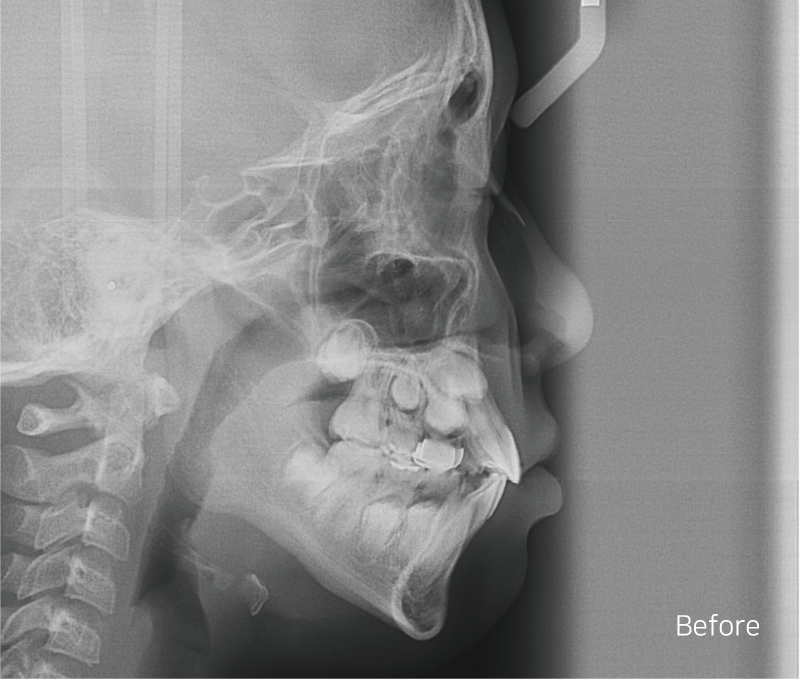

Before / after

상하악 Clippy-C (클리피씨) 전체 교정

구치부 반대교합은 통상적으로 비발치 교정일 경우에는

1년~1년 반 정도 교정 기간을 생각하고 있었어요-:D

안 모의 변화 모습이에요.

상/하악 전치 모두 상당량이 후방으로 이동이 되었기

때문에 훨씬 심미적으로 변화가 되었어요.